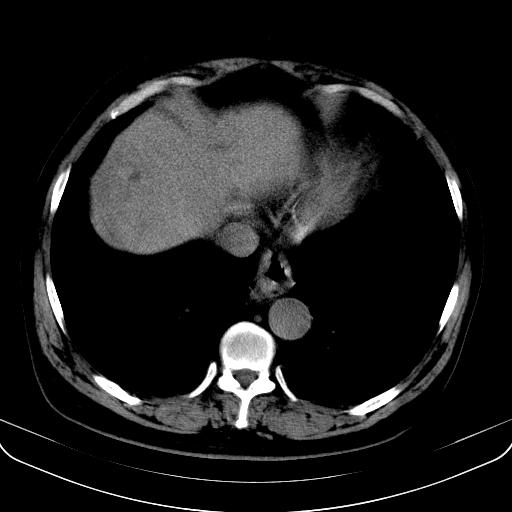

以下是引用jia119在2008-3-5 13:31:00的发言:[br]肝内多发片状低密度影,密度不均,我还是考虑肝ca可能,另肝内小囊肿,胆囊增大。

以下是引用形影不离在2008-3-5 12:18:00的发言:[br]肝硬化伴门脉高压征,肝内占位待排,增强再说.

以下是引用随光逐影在2008-3-5 21:11:00的发言:[br]肝硬化伴门脉高压(食管下段静脉曲张),肝癌不排除。建议:行ct增强扫描检查。

以下是引用同在2008-3-5 13:56:00的发言:[br]考虑肝癌可能性大,胆囊增大.